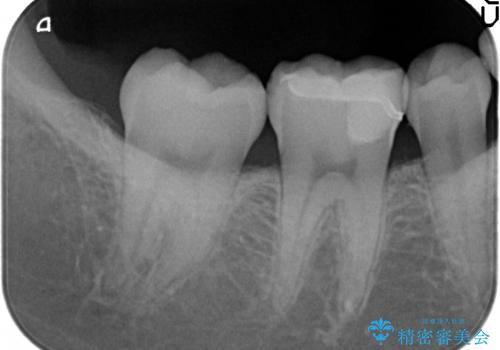

- 右下6番目の歯がしみるといらっしゃった方の症例です。

古い樹脂及び虫歯を除去後、セラミックインレーにて修復を行いました。